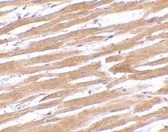

Below: Immunohistochemistry of GPVI in human heart tissue with GPVI antibody at 10 μg/ml.